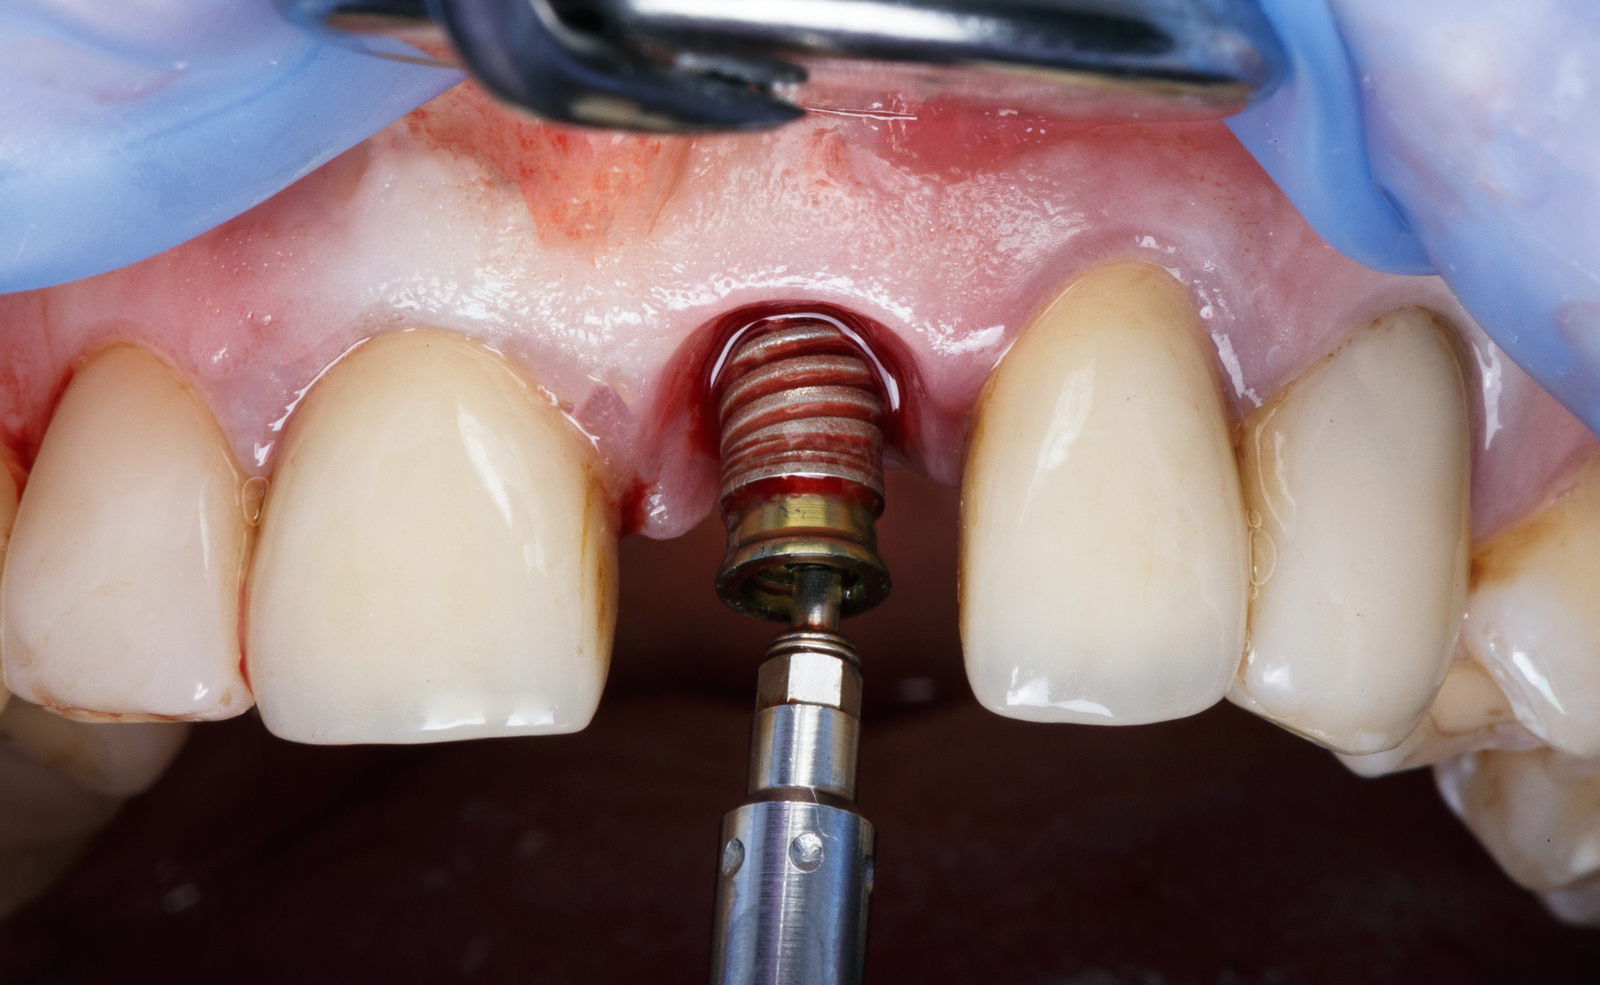

Un implante dental es una pequeña pieza de titanio que actúa como raíz artificial y se integra en el hueso maxilar mediante un proceso llamado osteointegración.

Sobre este implante se coloca posteriormente una corona dental, diseñada a medida para integrarse perfectamente con el resto de tus dientes.

En nuestra clínica trabajamos con implantes Straumann®, referencia mundial en implantología por su fiabilidad, precisión y biocompatibilidad.

Las coronas sobre implante son la parte visible del tratamiento y cumplen una función tanto estética como funcional.

Diseñamos cada corona de manera individual para:

Utilizamos materiales de alta calidad que ofrecen resistencia, naturalidad y larga duración.